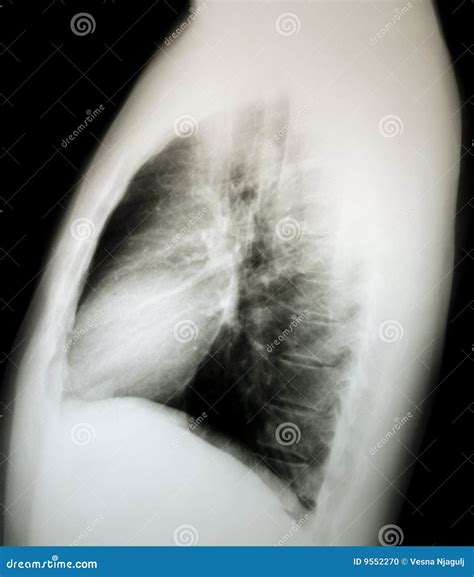

Procedure for a Normal Chest Ray

The procedure for a Normal Chest Ray is simple and usually takes only a few minutes. Here are the steps involved:

• Positioning: The patient stands or sits in front of the X-ray machine. The technician may ask the patient to take a deep breath and hold it briefly to ensure a clear image.

• Exposure: The X-ray machine emits a low-dose X-ray beam that passes through the chest and is captured on a detector.

• Image Capture: Multiple images may be taken from different angles to provide a comprehensive view of the chest cavity.